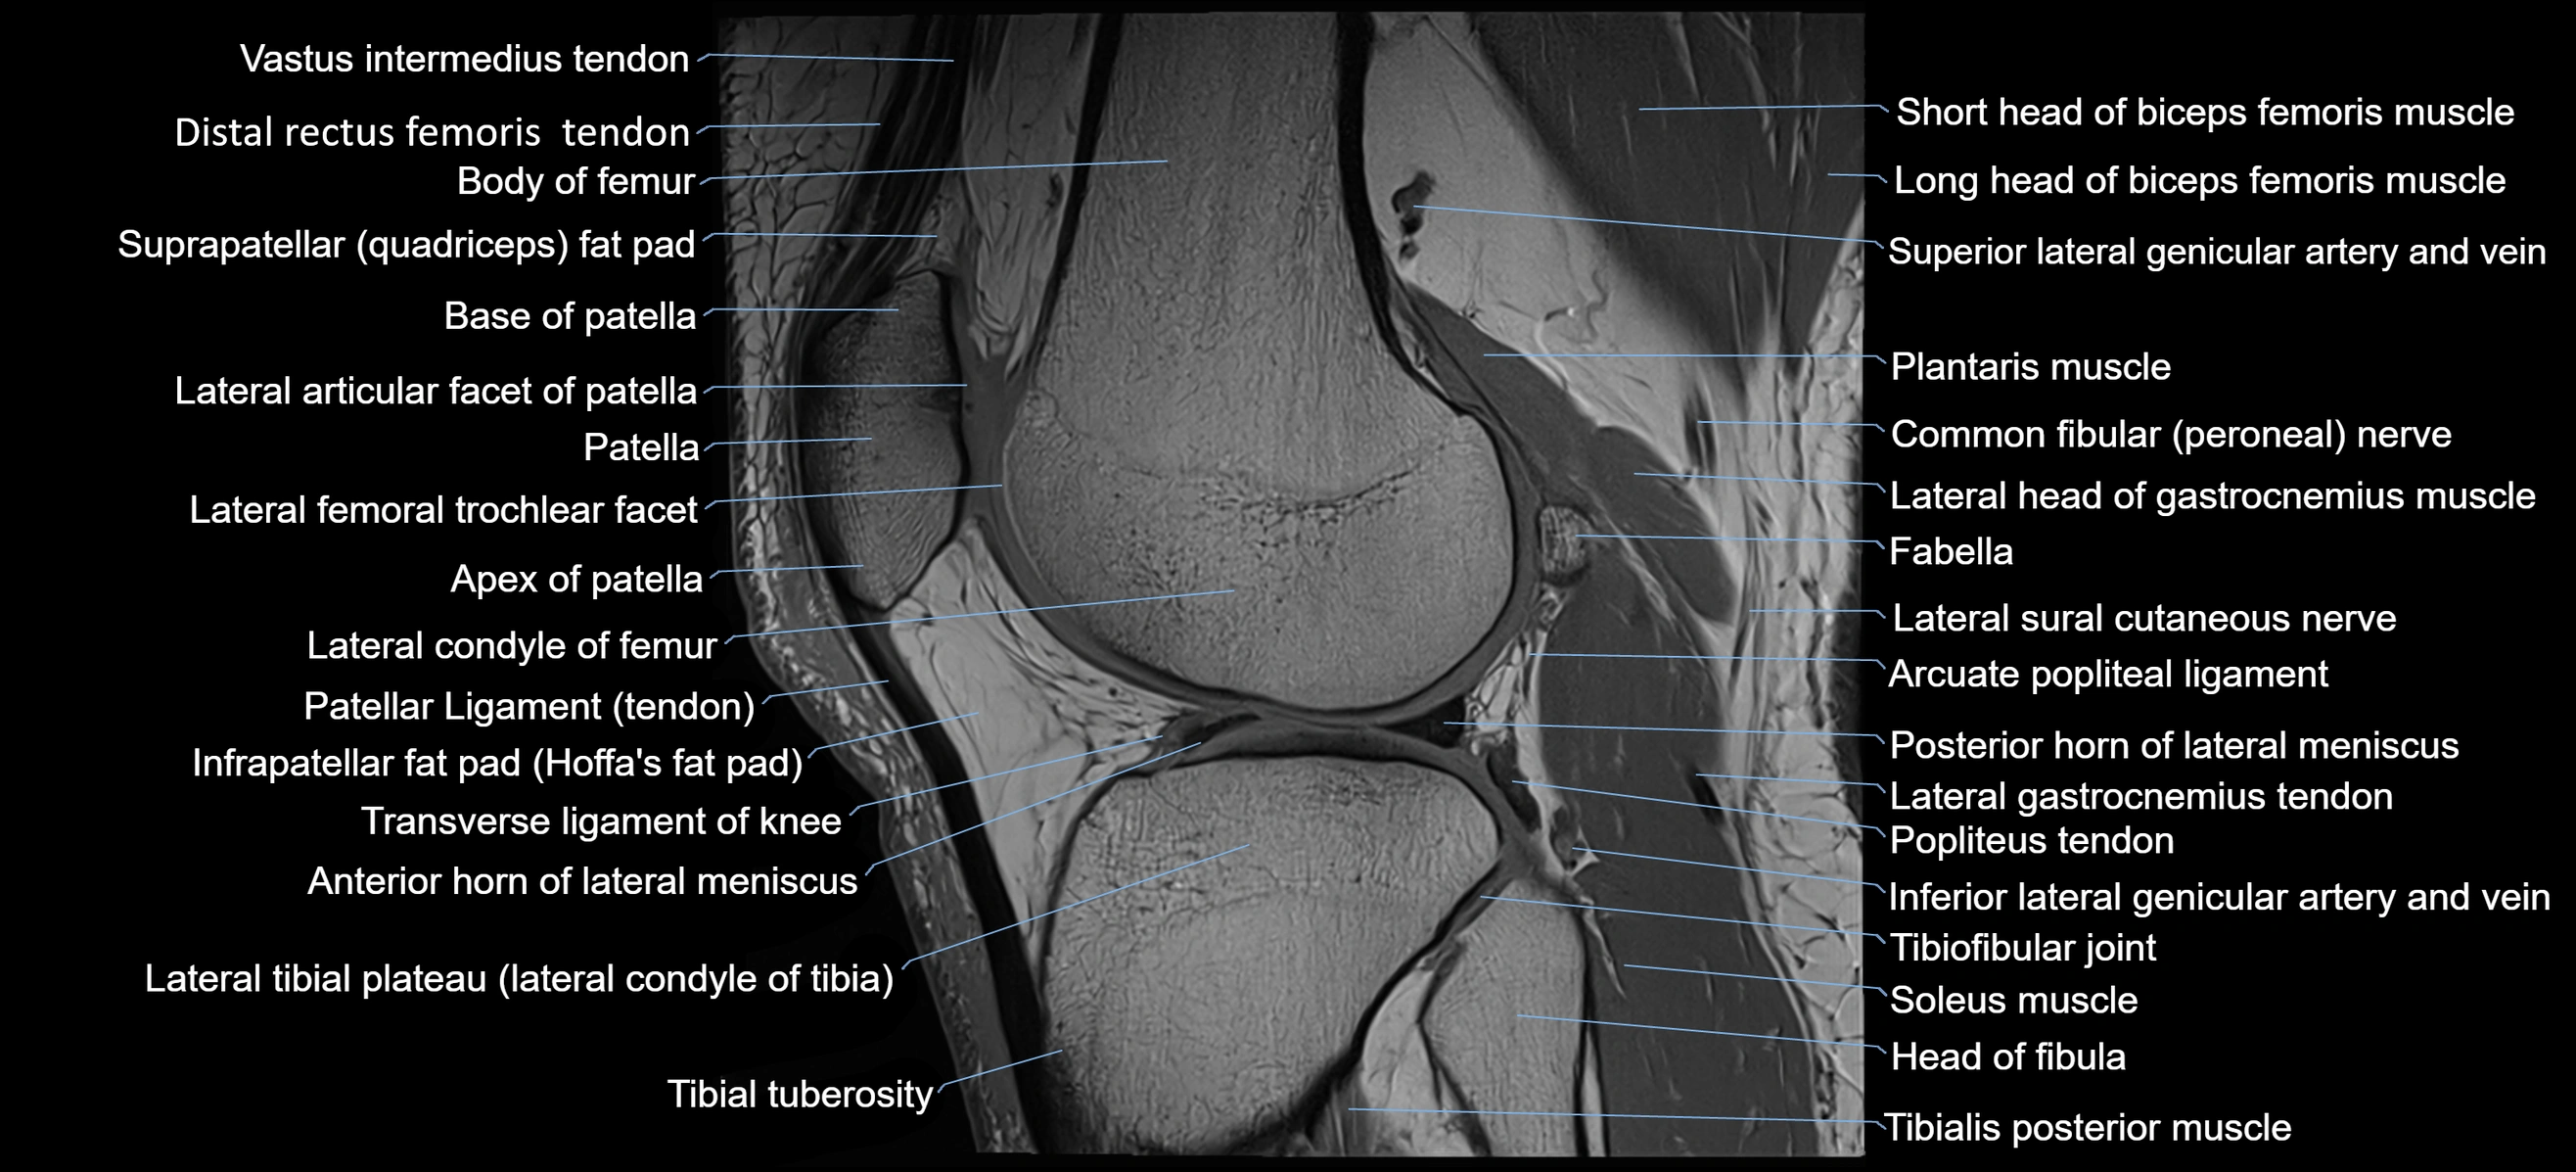

- Anterior horn of lateral meniscus

- Apex of patella

- Base of patella

- Distal rectus femoris tendon

- Distal vastus intermedius tendon

- Head of fibula

- Infrapatellar fat pad

- Lateral articular facet of patella

- Lateral condyle of femur

- Lateral gastrocnemius tendon

- Lateral head of gastrocnemius muscle

- Lateral sural cutaneous nerve

- Oblique popliteal ligament

- Patellar tendon (patellar ligament)

- Plantaris muscle

- Popliteus tendon

- Posterior horn of lateral meniscus

- Soleus muscle

- Suprapatellar fat pad

- Tibial tuberosity

- Transverse ligament of knee